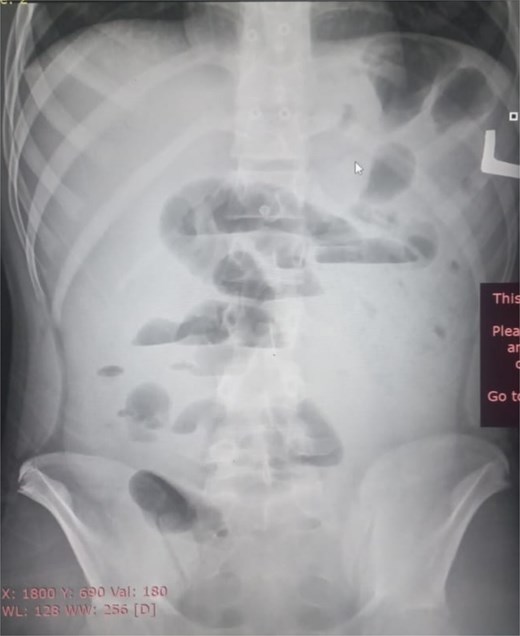

Initial radiographic evaluation with a plain abdominal X-ray confirmed the clinical suspicion of acute intestinal obstruction, demonstrating multiple air-fluid levels and diffuse small bowel dilatation (Fig. 1). To further delineate the underlying etiology, a contrast-enhanced computed tomography (CECT) scan was performed; providing critical diagnostic information it revealed, in the right iliac fossa, a striking encapsulation of the small intestine loops within a sac-like membrane, accompanied by ascites. This constellation of findings formed a pathognomonic cocoon-like structure (Fig. 2). Furthermore, the CECT identified a concurrent gut malrotation, evidenced by a left-sided displacement of the colon (Fig. 3). Laboratory findings showed an elevated total leukocyte count (TLC) of 21 000, indicative of inflammation, while other parameters were within normal limits. The patient underwent an exploratory laparotomy. Intraoperatively, the abdominal viscera were encased within a thick fibrous membrane (Fig. 4), containing ascitic fluid. The membrane was incised, adhesiolysis was performed, and the entrapped small bowel loops were released, and then a kink in the small intestine causing obstruction was identified and corrected. Additionally, the appendix was found to be secondarily involved in the encapsulating process. It was encased in the dense fibrocollagenous membrane, forming an inflammatory mass consistent with chronic serositis and localized fibrosis, rather than a classic acute appendicular phlegmon. Based on this intraoperative assessment that the mass was a manifestation of the cocoon’s chronic inflammation, a simple appendectomy was performed instead of a more extensive right hemicolectomy. This procedure was necessary to achieve complete release of the entrapped bowel, remove this localized inflammatory focus, and obtain a specimen for histopathology to definitively rule out a primary appendiceal pathology as a secondary cause of the peritonitis. Furthermore, ascitic fluid analysis showed no bacterial or mycobacterial growth, ruling out tuberculosis and the histopathological examination confirmed the fibrocollagenous nature of the membrane. The patient recovered well postoperatively and was discharged on the sixth day with advice for a follow-up after 2 weeks. At the follow-up visit, he reported no symptoms, and abdominal imaging confirmed the absence of obstruction. Histology further confirmed the benign fibrous nature of the membrane, with no signs of malignancy.

Intraoperative findings of idiopathic Sclerosing encapsulating peritonitis. The image displays the abdominal viscera entirely encased within a smooth, thick, cocoon-like sac, consistent with abdominal cocoon syndrome. The whitish, glistening appearance of the membrane is characteristic of its dense, fibrocollagenous composition, which was later confirmed by histopathology.